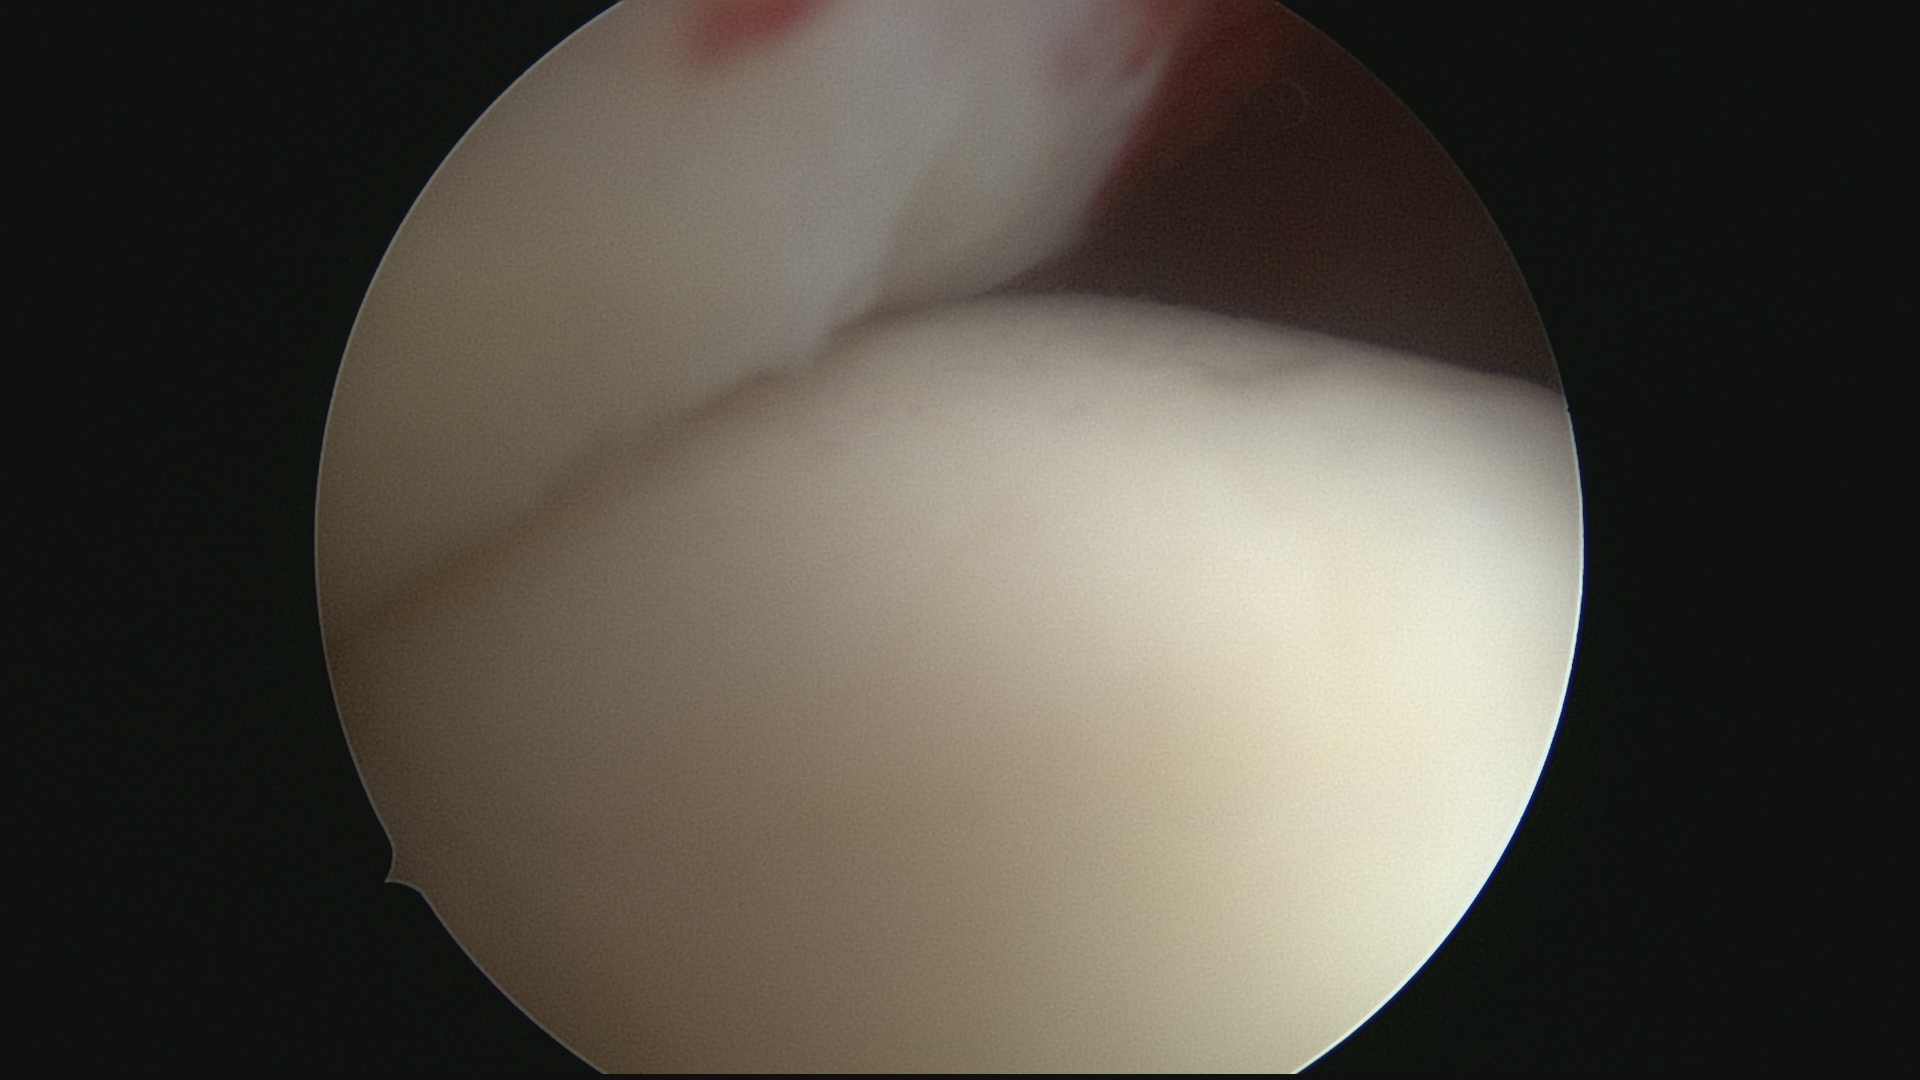

Réinsertion terminée (Vue sous acromiale)

Réinsertion coiffe (Vue endoarticulaire)